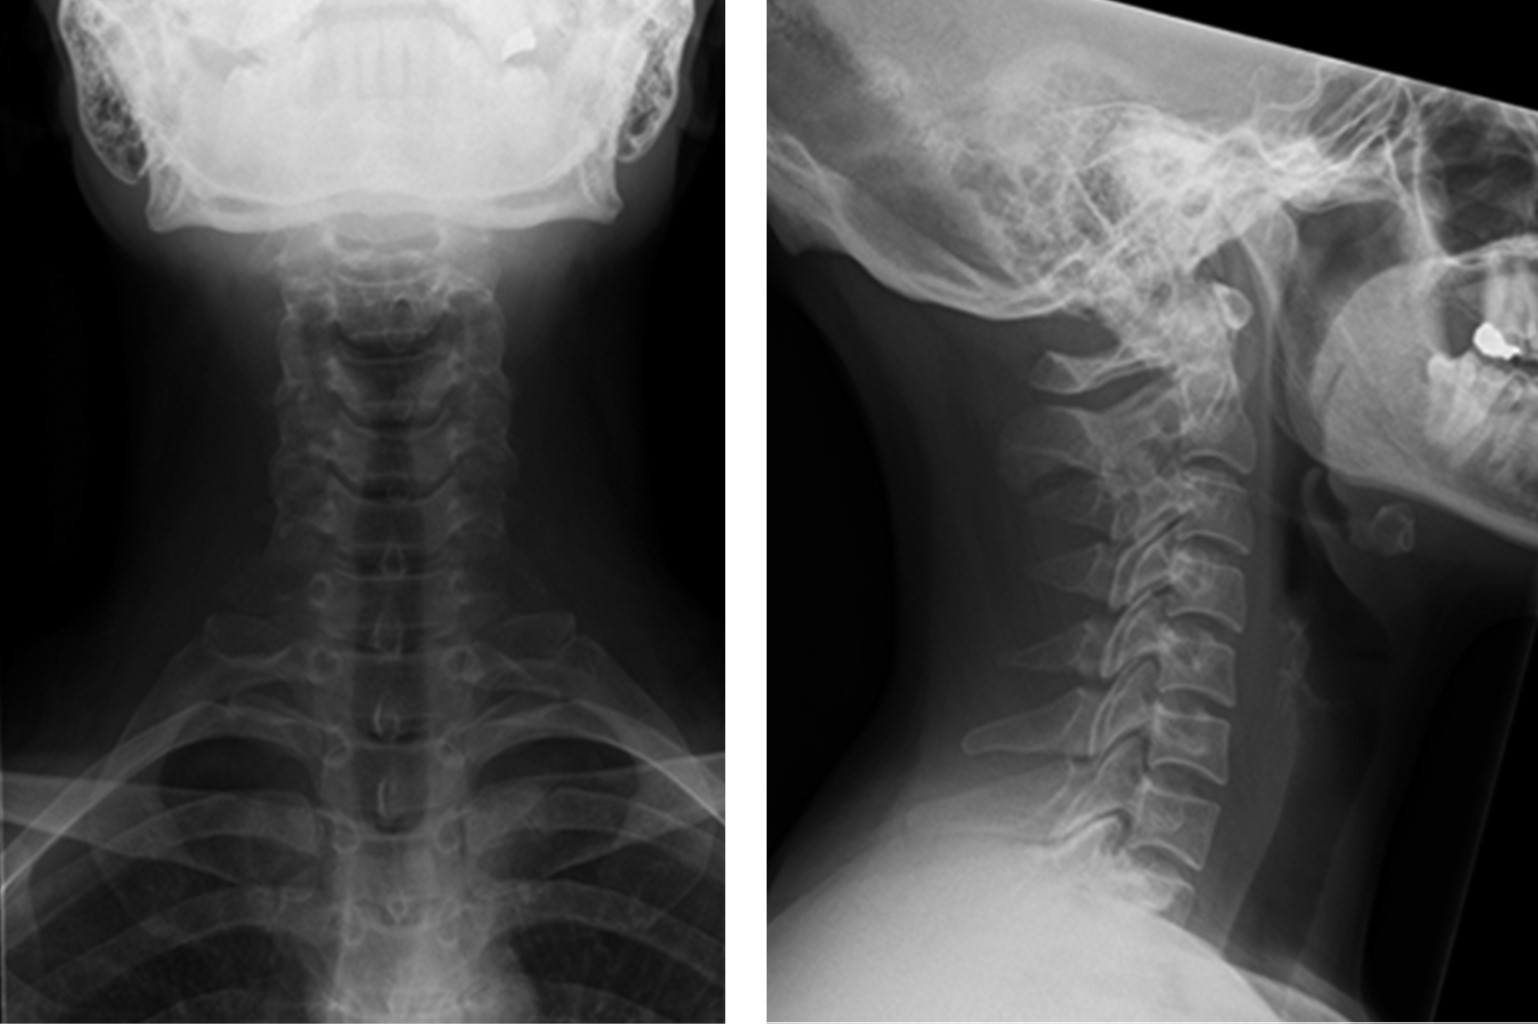

In June 2011 she was referred for an orthopedic review. In July the same year she was diagnosed with a C5-6 left foraminal herniation and started non-operative treatment with physiotherapy. The herniation was compressing left C6 nerve root as seen on MRI (Figures 1 and 2). During the treatment she stated that just mild relief was achieved during neck traction, worsening immediately after. She did seek spinal specialist opinion in August 2011, suffering from an intensive neck and left arm pain with sensitivity loss and transient motor deficit. The motor deficit would occur during her practice when she raised her arm toward the head for protection. Every time the guard was set, a sudden pain would appear with loss of power in the arm and hand, dropping both and dismounting her protection. This deficit would put her in further danger from a blow struck from her opponent to the head.

Three weeks after procedure, with a healed wound and a stable TDR (Figure 3A-D) she was allowed to return to training along with a rehabilitation program. Three months after surgery the patient competed in the world champion winning a medal, losing only the title fight and at that time and more importantly, having no symptoms during and after that event.